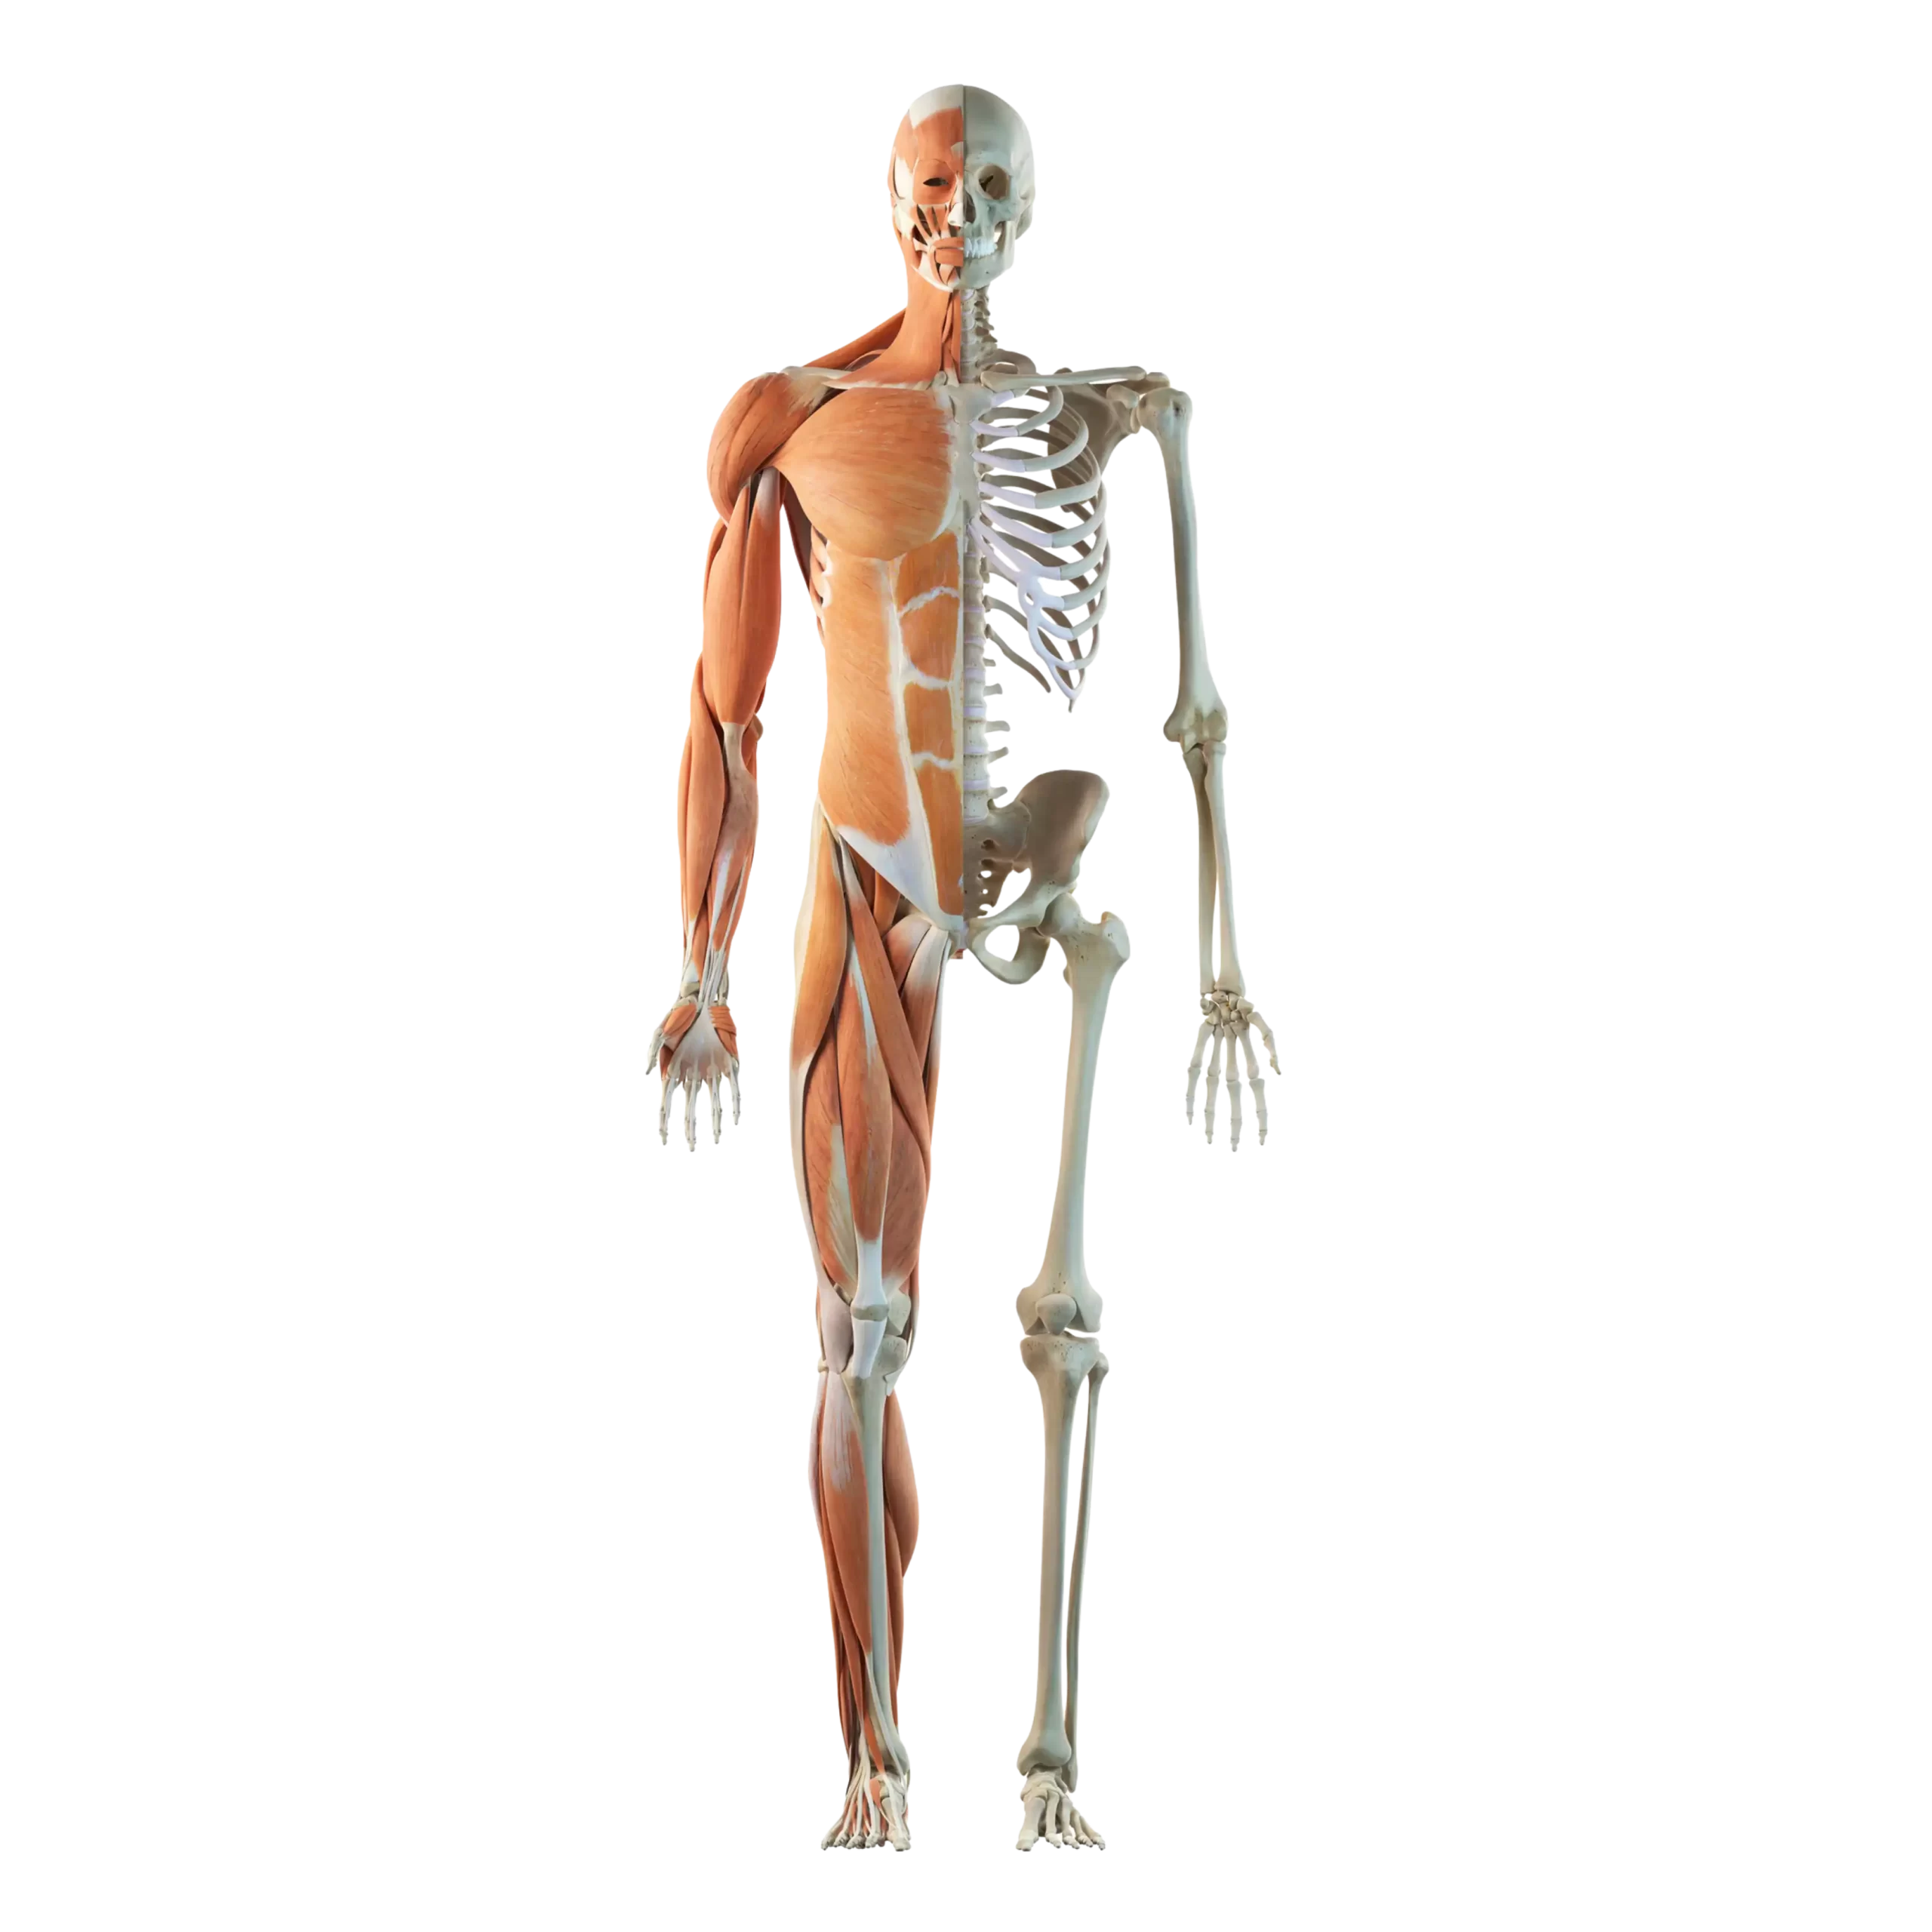

Head & Mind

Specialized care for Migraines, Insomnia, Depression, Bell’s Palsy, and Stroke recovery.

Neck & Cervical

Relief for Chronic Pain, Stiffness, Torticollis, Adenopathies (in kids) and Disc Degeneration.

Shoulder & Upper Arm

Treatment for Frozen Shoulder, Rotator Cuff tears, and Bicipital Tendonitis.

Elbow & Forearm

Focused recovery for Epicondylitis, Arm Pain, and Paresthesias (numbness).

Wrist & Hand

Effective management of Carpal Tunnel Syndrome, Osteoarthritis, and Joint Pain.

Lower Back & Spine

Support for Sciatic Pain, Herniated Discs, Scoliosis, and Spinal Stenosis.

Hip

Care for Iliopsoas Tendonitis, Piriformis Syndrome, and Fibromyalgia.

Abdomen

Irritable Bowel Syndrome, Constipation, Gastrooesophageal Reflux Disorder, Abdominal Sphincter Incompetence

Chest/Ribs

Upper & Lower Respiratory Infection, Allergic Cough, Mechanical Rib Pain &

Non cardiac chest pain

Knee & Leg

Recovery for Sports Injuries, Meniscus/Ligament tears, and Arthritis.

Ankle & Foot

Solutions for Plantar Fasciitis, Heel Pain, and Peripheral Neuropathy.